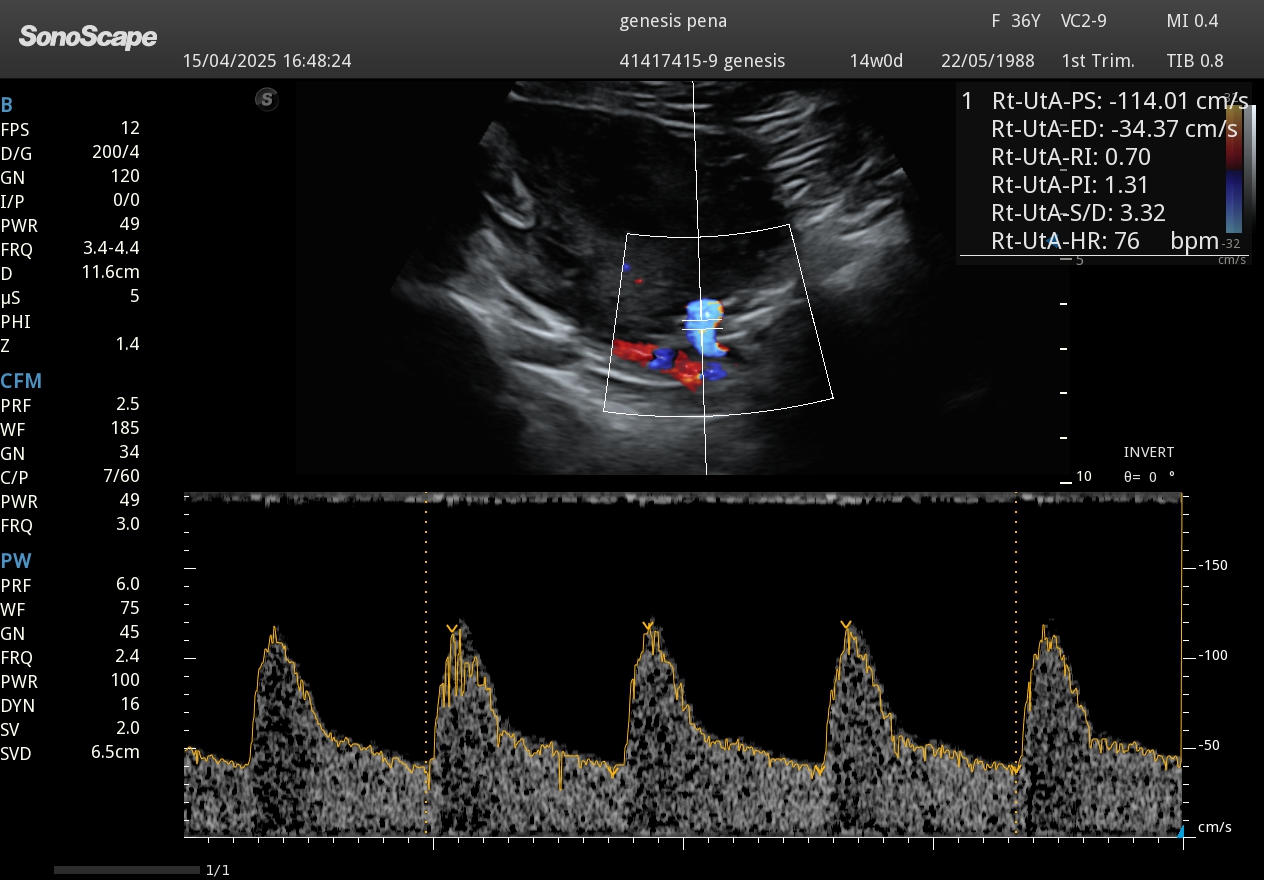

Ecografía Doppler flujo uterino embarazo

Evaluación Doppler color del flujo uterino para monitoreo temprano.